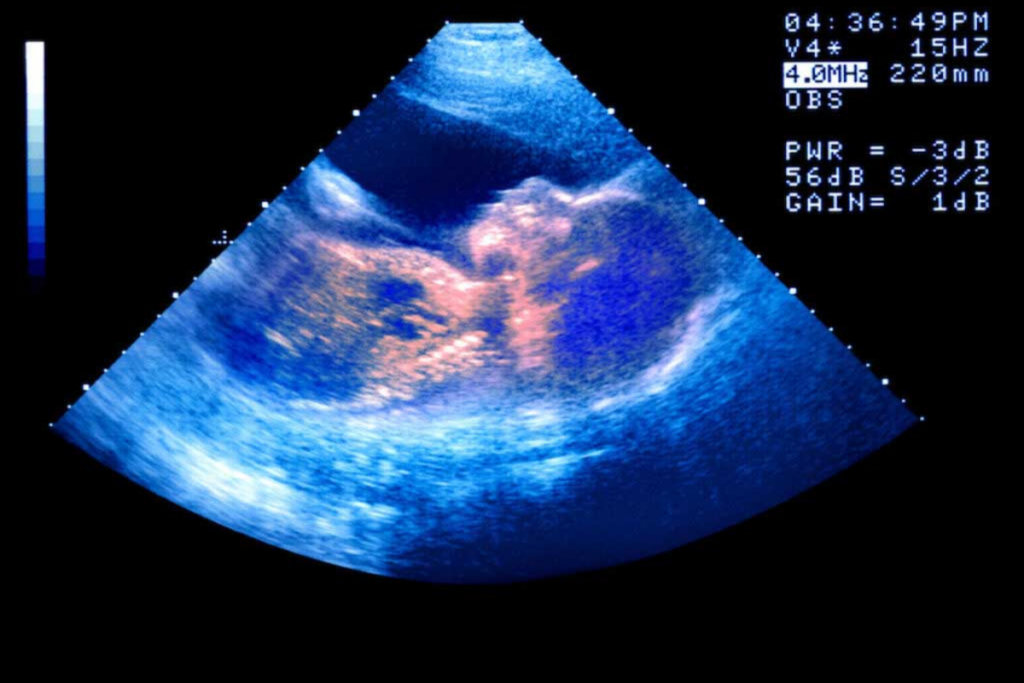

Post Topic: Pregnancy and Birth Complications